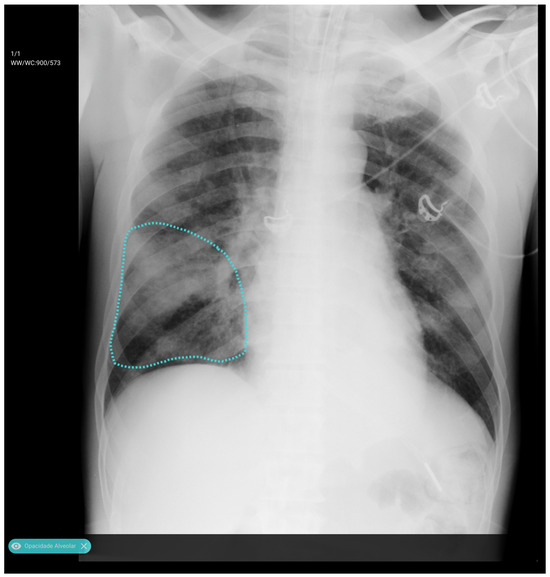

We employed a U-Net architecture with a MobileNetV2 backbone to segment the thoracic region and generate a unified “tongue-shaped” mask encompassing both lungs as well as the mediastinal and hilar regions. We chose U-Net for its proven effectiveness in medical image segmentation tasks, where high spatial precision is required. Its encoder–decoder “U” structure enabled the capture of both contextual and spatial information, facilitating the delineation of complex anatomical structures with high resolution. In this study, segmentation was used not only to isolate the relevant pulmonary region but also to constrain the subsequent classifier’s focus to clinically meaningful areas, thereby improving accuracy and reducing noise from irrelevant image regions.

We resized input images to 512 × 512 pixels and performed data augmentation using geometric and photometric transformations (padding, Gaussian noise, CLAHE, brightness/gamma adjustment, blur, motion blur, and hue/saturation shifts). The model was trained for 40 epochs with a batch size of 8 using the Adam optimizer (initial learning rate = 5 × 10−5) and a composite loss function combining Dice loss and binary focal loss to balance region overlap and class imbalance. Performance was monitored using Intersection over Union and F-score metrics, and the best model was selected by minimizing the validation loss with adaptive learning rate scheduling. Figure 2 illustrates the resulting mask, which ensures inclusion of central thoracic structures.

Figure 2. Example of first-stage segmentation: the generated “tongue-shaped” mask covering both lungs and mediastinal structures.